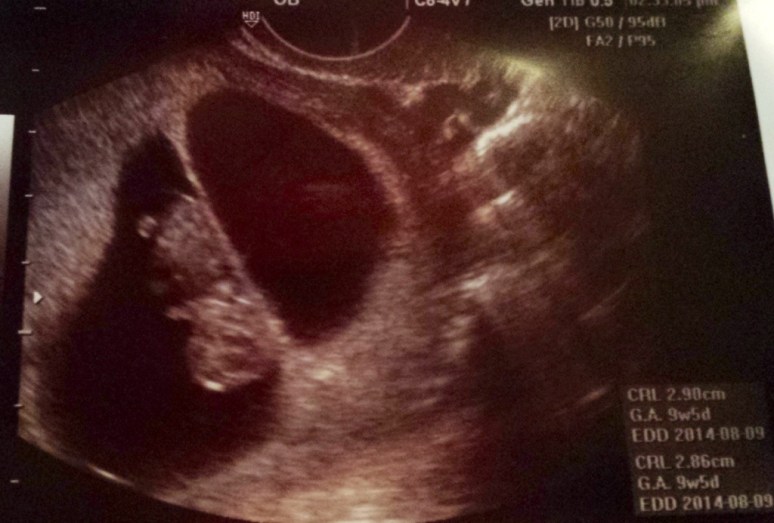

This past Thursday, January 9, 2014 was our first OB appointment. I was at the office for 3 hours, but I didn’t mind because I still can’t believe that I was even there. The sweet sweet nurse (who happens to be a friend and co-worker of my girlfriend who just had twins in December) met with me first and went thoroughly through my paperwork, then I met with my new OB (I use to see another Dr. in the group practice, but he has since retired) and again she was very sweet and thorough. My Dr. wanted to do another ultrasound (I had to ask if it was safe since it was my third one in about 2 1/2 weeks) and I got to see the babies again! Unfortunately, Hubby had to work and was unable to make it to this appointment. Baby B was dancing around like crazy, they both have little hands and feet now and I swear that Baby B was fist pumping. Lastly I had my blood drawn, I had to get poked twice, the first phlebotomist couldn’t get my blood flowing and sent me out into the waiting area with a glass of water, second time was a charm. Thank goodness!

More pictures of the little ones:

Baby A-Head up

Baby B-Head down